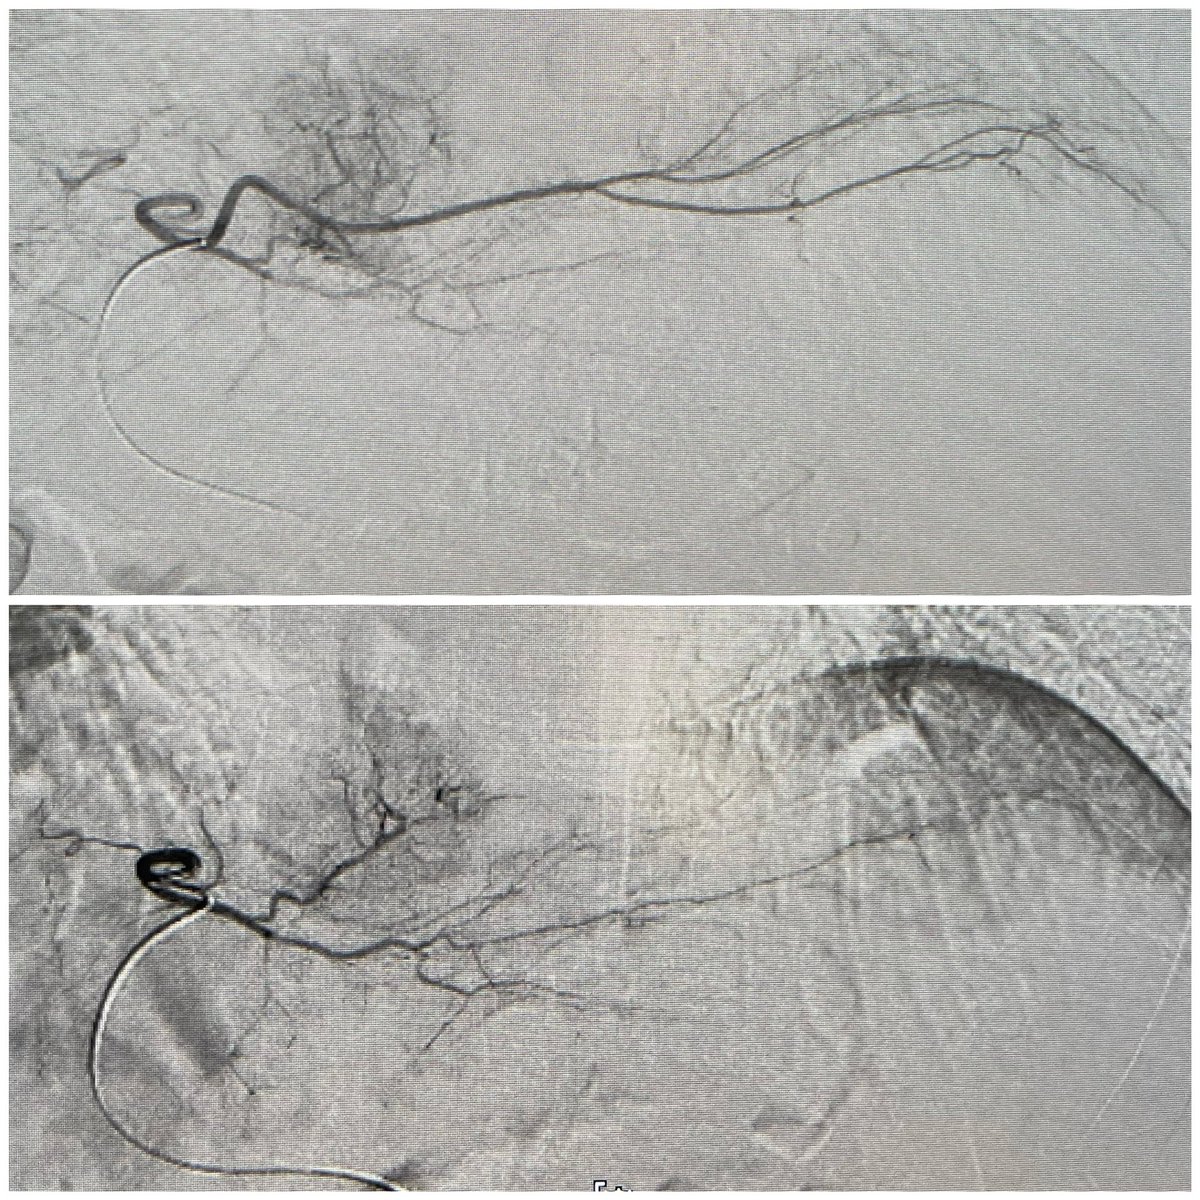

Patient with multiple small arterial ulcers involving the toes 1-3 with poor runoffs. Targeted recanalization of the AT with great flow to the wound. This patient will be plugged into our clinic and watched closely to assess healing.

0

5